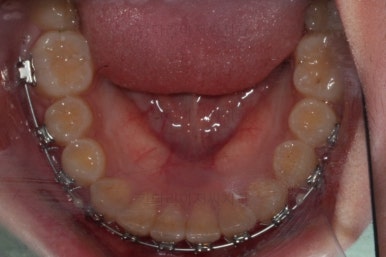

마무리 때의 모습입니다.

임시 개념으로 치아 사이즈를 키운건데 환자분은 만족하시나봐요.

보통 올세라믹, 라미네이트 등 보철치료는 성인이 되어서 해야해서 이래나 저래나 이정도에서 만족하기로 했습니다.

치아는 매우 가지런해졌고 뾰족하던 앞니의 형태도 좋아졌어요.

매복되어 있던 송곳니도 잘 나왔고 과개교합도 물론 개선이 되었습니다.

부산교정치과 키다리아저씨치과에서 치료한 이번 치료의 전후사진을 비교해 볼게요.

왼쪽이 치료 전, 오른쪽이 치료 후 모습입니다.

매우 복잡한 문제들을 복합적으로 가지고 있었던 경우였지만 만족할만한 결과를 얻을 수 있었어요.